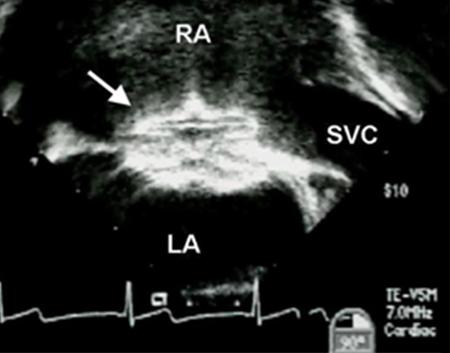

Treatment involves either an operation or percutaneous device closure.[29][Figure caption and citation for the preceding image starts]: Transesophageal echocardiographic image of an ASD occluder device (arrow). (RA) right atrium; (LA) left atrium; (SVC) superior vena cavaImage courtesy of Patrick W. O'Leary, MD [Citation ends].